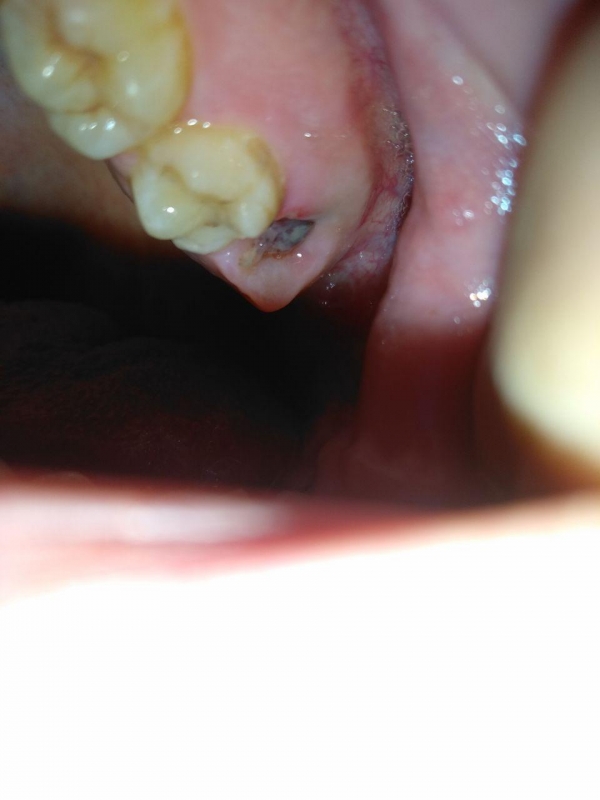

В пятницу утром мне удалили зуб мудрости. Все прошло хорошо, кровь достаточно быстро остановилась, обезболивающих не принимал даже после удаления зуба. Каждый день лунку обрабатывал Хлоргексидином. Болей нет, первые два дня были только ощущения вкуса крови во рту. Сегодня решил посмотреть, как идет заживление, смутил цвет.

Это нормально или похоже на нагноение?

Похоже на фибринозный налет, он сопровождает регенерацию лунки.